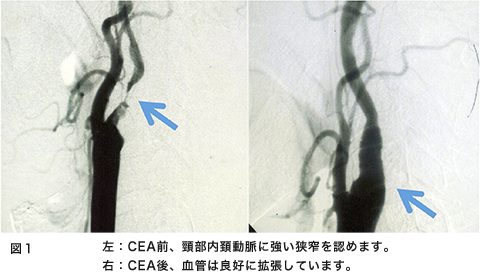

脳の血管が急につまって倒れてしまう病気が脳梗塞です。脳梗塞は様々な原因があるのですが、その一つとして頚部内頚動脈狭窄があります。これは糖尿病、高血圧症、喫煙、高脂血症といった生活習慣病が動脈硬化をきたし、頚部の内頚動脈が細くなり、ここに血栓(小さな血のかたまり)が形成され血液の流れに乗って脳まで流れて脳の血管を詰まらせる、または血管が細くなることで脳の血の巡りが悪くなり脳梗塞を発症します(図1左、図2)。

検査は頚動脈エコー、頸部血管MRA、または血管撮影などがあります。この検査の選択は各施設によって異なります。これらの検査で強い動脈狭窄が発見されたら患者さまと相談して手術治療を考えていくことになります。この手術を頚動脈内膜血栓摘出術(CEA)といいます。簡単に説明すると、動脈硬化で細くなった血管を広げて、脳梗塞の原因となる血の塊(血栓)を取り去ってしまう手術です(図1、図3)。現在最も安全性と治療効果に優れている方法です。この手術の適応で興味のあるところは施設の手術成績によって適応が決定されることです。症状が出現した内頚動脈狭窄症に対してはCEAの合併症が6%以下の施設での手術が有効性であるとされています。別の言い方をするとCEAの合併症が6%以上の施設、術者はこの手術をやってはいけないことになります。